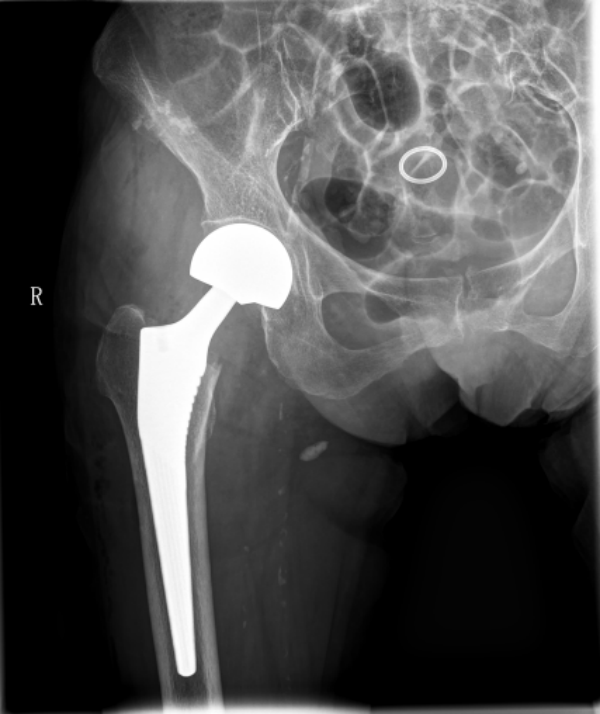

面对这一困境,烟台业达医院骨三科副主任张春刚立即组织多学科会诊,邀请麻醉科、心内科、呼吸内科、营养科等相关科室专家,对老人的身体状况进行全面评估。经过反复讨论和严谨论证,大家认为:虽然手术风险巨大,但只要术前做好充分准备、术中精准操作、术后精心护理,就能为老人争取到康复的机会,让她摆脱长期卧床的痛苦。最终,在与家属充分沟通并获得理解与信任后,医疗团队决定为姜奶奶实施 “右侧人工股骨头置换术”。

手术当天,在麻醉科团队的密切监测下,手术正式开始。骨三科副主任张春刚带领团队凭借丰富的临床经验和精湛的手术技艺,在狭小的手术视野内精准操作:消毒、铺巾、切开、暴露骨折部位、清除坏死组织、植入人工股骨头假体、复位、缝合……整个手术过程有条不紊,历时仅1小时便顺利完成。术中,老人生命体征平稳,出血量极少,各项指标均在正常范围内。